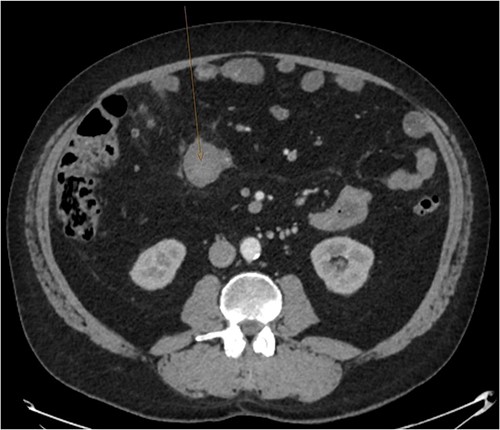

A CT abdomen-pelvis (CT-AP) revealed an acute haematoma inferolateral to the third part of the duodenum and another at the root of the mesentery. High density fluid related to the mesenteric bleed was also seen extending from the right para-colic gutter into the pelvis and in the peri-hepatic region. The patient was admitted under general surgery, stabilized with intra-venous fluid resuscitation, co-amoxiclav and metronidazole and cross matched for four units of blood. A CT-angiogram demonstrated acute haemorrhage throughout the abdomen with a 104 x 62 mm haematoma arising centrally at the level of L2 within the mesenteric fat (Fig. 1). The haematoma did not appear to originate from any specific mesenteric vessels but was related to some mid and distal jejunal loops. The angiogram also showed discontinuity when tracing the proximal and mid jejunal loops inferiorly, extensive haemorrhagic peritoneal fluid around the liver extending inferiorly (Fig. 2) and a small amount of peri-splenic haemorrhagic fluid. Curved reformatting of the angiogram revealed no abnormalities within the superior mesenteric artery (Fig. 3).

Curved reprogramming of the initial CT angiogram. Curved reprogramming of the patient’s initial CT angiogram showed no evidence of an aneurysm within the superior mesenteric artery, effectively ruling this out as a cause of the patient’s acute bleed.